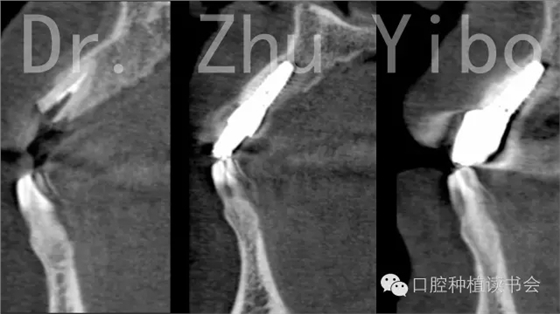

術前術后CBCT對比測量示:唇側牙槽骨穩(wěn)定(圖13)。術前術后石膏模型掃描,數(shù)字軟件重合對比測量:唇側牙齦組織穩(wěn)定(圖14)。

圖13